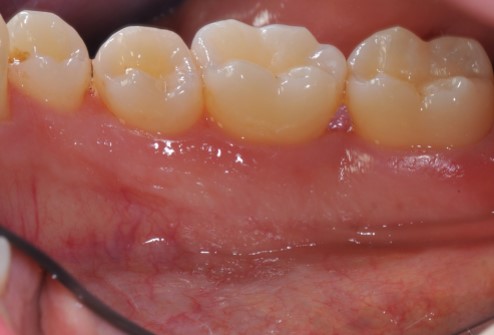

01/22 - Pre-surgical clinical situation, buccal view.

Deep intrabony defects treated using Straumann® Emdogain® - Dr. M. Stefanini